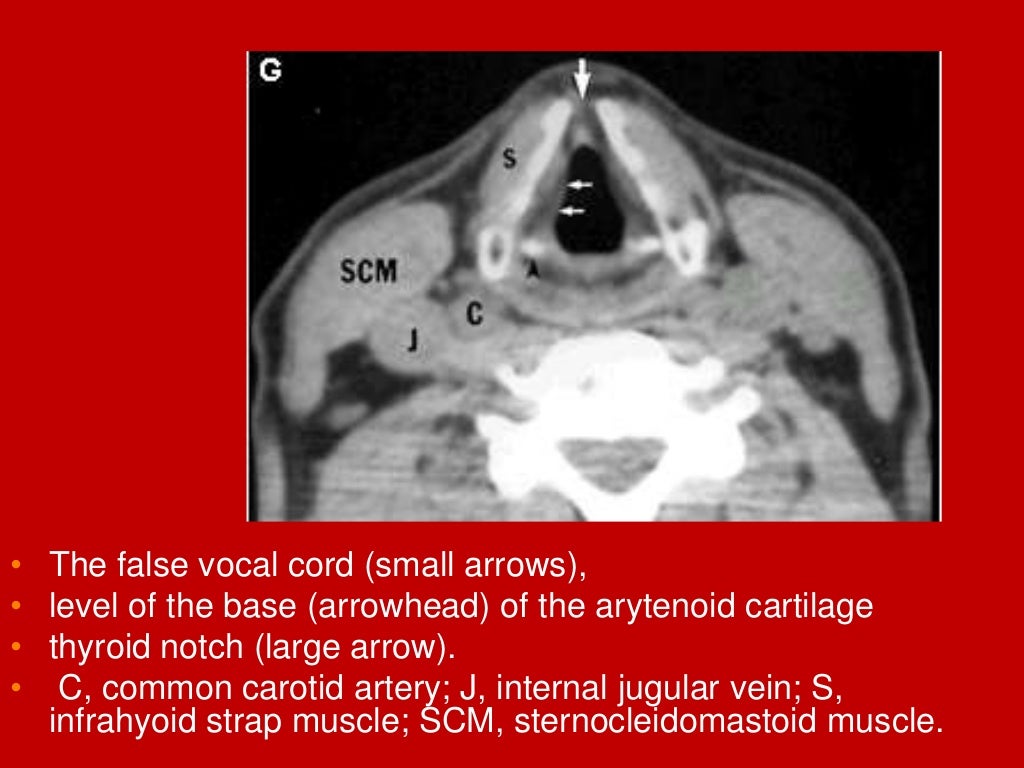

Mri Anatomy Larynx . It acts as a critical connection between the oropharynx above and the trachea below serving essential functions such as respiration, phonation and preventing aspiration. The larynx is a mucosa lined tube supported by a cartilaginous and muscular framework ably supported by multiple ligamentous and membranous structures. This chapter begins with a section on anatomy, including the normal appearance in the various imaging planes. (a) ct image of the soft tissue window on the sagittal plane of larynx; The larynx consists of a cartilage skeleton, as well as internal structures that are divided into three subsites,. The aim of this paper is to give a comprehensive radiological overview of larynx and hypopharynx complex anatomy, combining in vivo images,. A brief discussion of the technical. Provides a detailed review of radiological anatomy of the larynx. Ct and mri images of the sagittal plane of larynx. Mri is rarely used for laryngeal imaging, but may be valuable when assessment of laryngeal cartilage invasion is of critical importance. Presents imaging findings in benign and malignant disease.

Mri Anatomy Larynx The larynx consists of a cartilage skeleton, as well as internal structures that are divided into three subsites,. It acts as a critical connection between the oropharynx above and the trachea below serving essential functions such as respiration, phonation and preventing aspiration. Presents imaging findings in benign and malignant disease. This chapter begins with a section on anatomy, including the normal appearance in the various imaging planes. (a) ct image of the soft tissue window on the sagittal plane of larynx; The larynx is a mucosa lined tube supported by a cartilaginous and muscular framework ably supported by multiple ligamentous and membranous structures. Provides a detailed review of radiological anatomy of the larynx. Ct and mri images of the sagittal plane of larynx. The larynx consists of a cartilage skeleton, as well as internal structures that are divided into three subsites,. The aim of this paper is to give a comprehensive radiological overview of larynx and hypopharynx complex anatomy, combining in vivo images,. Mri is rarely used for laryngeal imaging, but may be valuable when assessment of laryngeal cartilage invasion is of critical importance. A brief discussion of the technical.